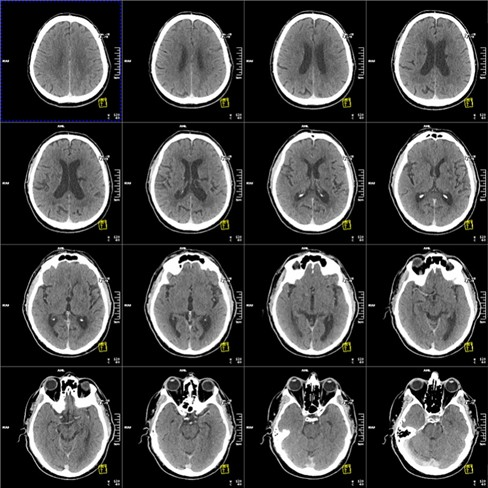

КТ головного и спинного мозга применяют для оценки расположения белого и серого вещества органа, выявления аномалий развития, воспалительных или ишемических процессов, опухолевых образований. Для лучшей информативности иногда применяют контрастные вещества.